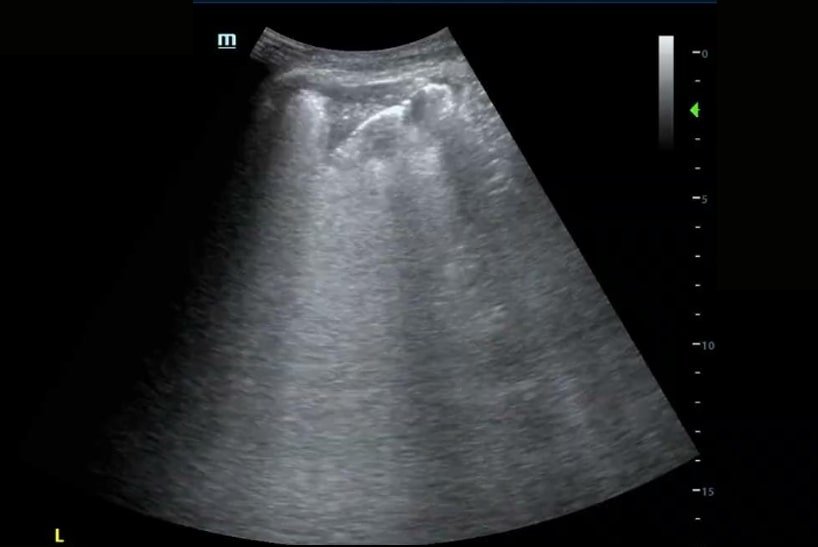

A 68-year-old male with known congestive heart failure (CHF) was seen for a new cough, increased dyspnea upon exertion, increased lower extremity edema and low-grade fever. Physical exam revealed bibasilar crackles, bilateral lower extremity edema, and weight gain above dry weight. A working diagnosis of acute decompensated heart failure exacerbation was made.

Bedside ultrasound revealed the expected diffuse B-lines in the bilateral posterior lower lung zones; however, it also found a consolidation in the left lower lung, seen here with the shred sign as well as a small pleural effusion. Therefore the patient was additionally treated for community-acquired pneumonia, which might not have been addressed without the use of point-of-care ultrasound (POCUS)!